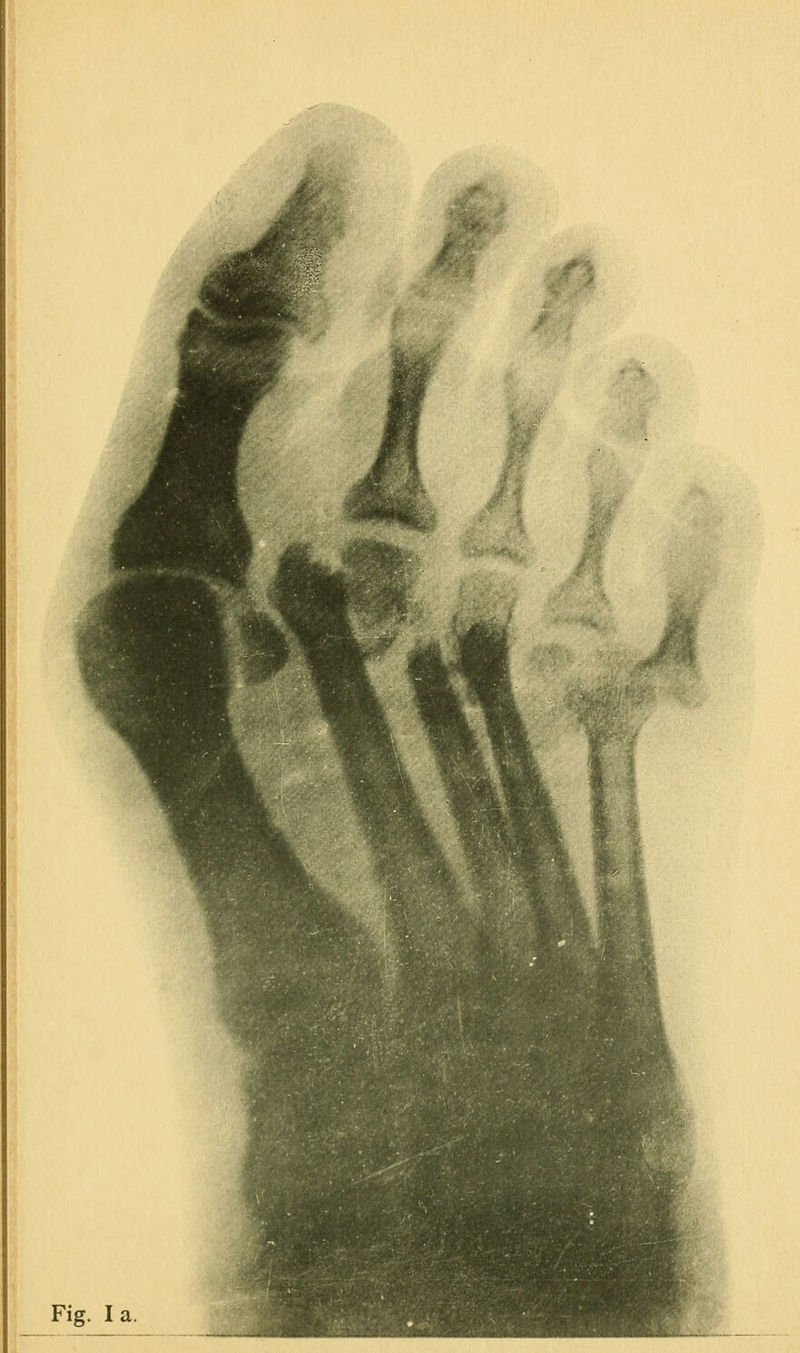

Credit: Seltene Verletzungen am Fussskelet. Source: Wellcome Collection.